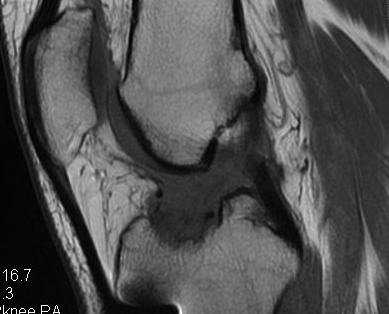

Knee > Hip

- superficial position

- limited cover of well vascularised muscle

- watershed area of skin blood supply anterior to the skin incision

- much increased in fully constrained prosthesis